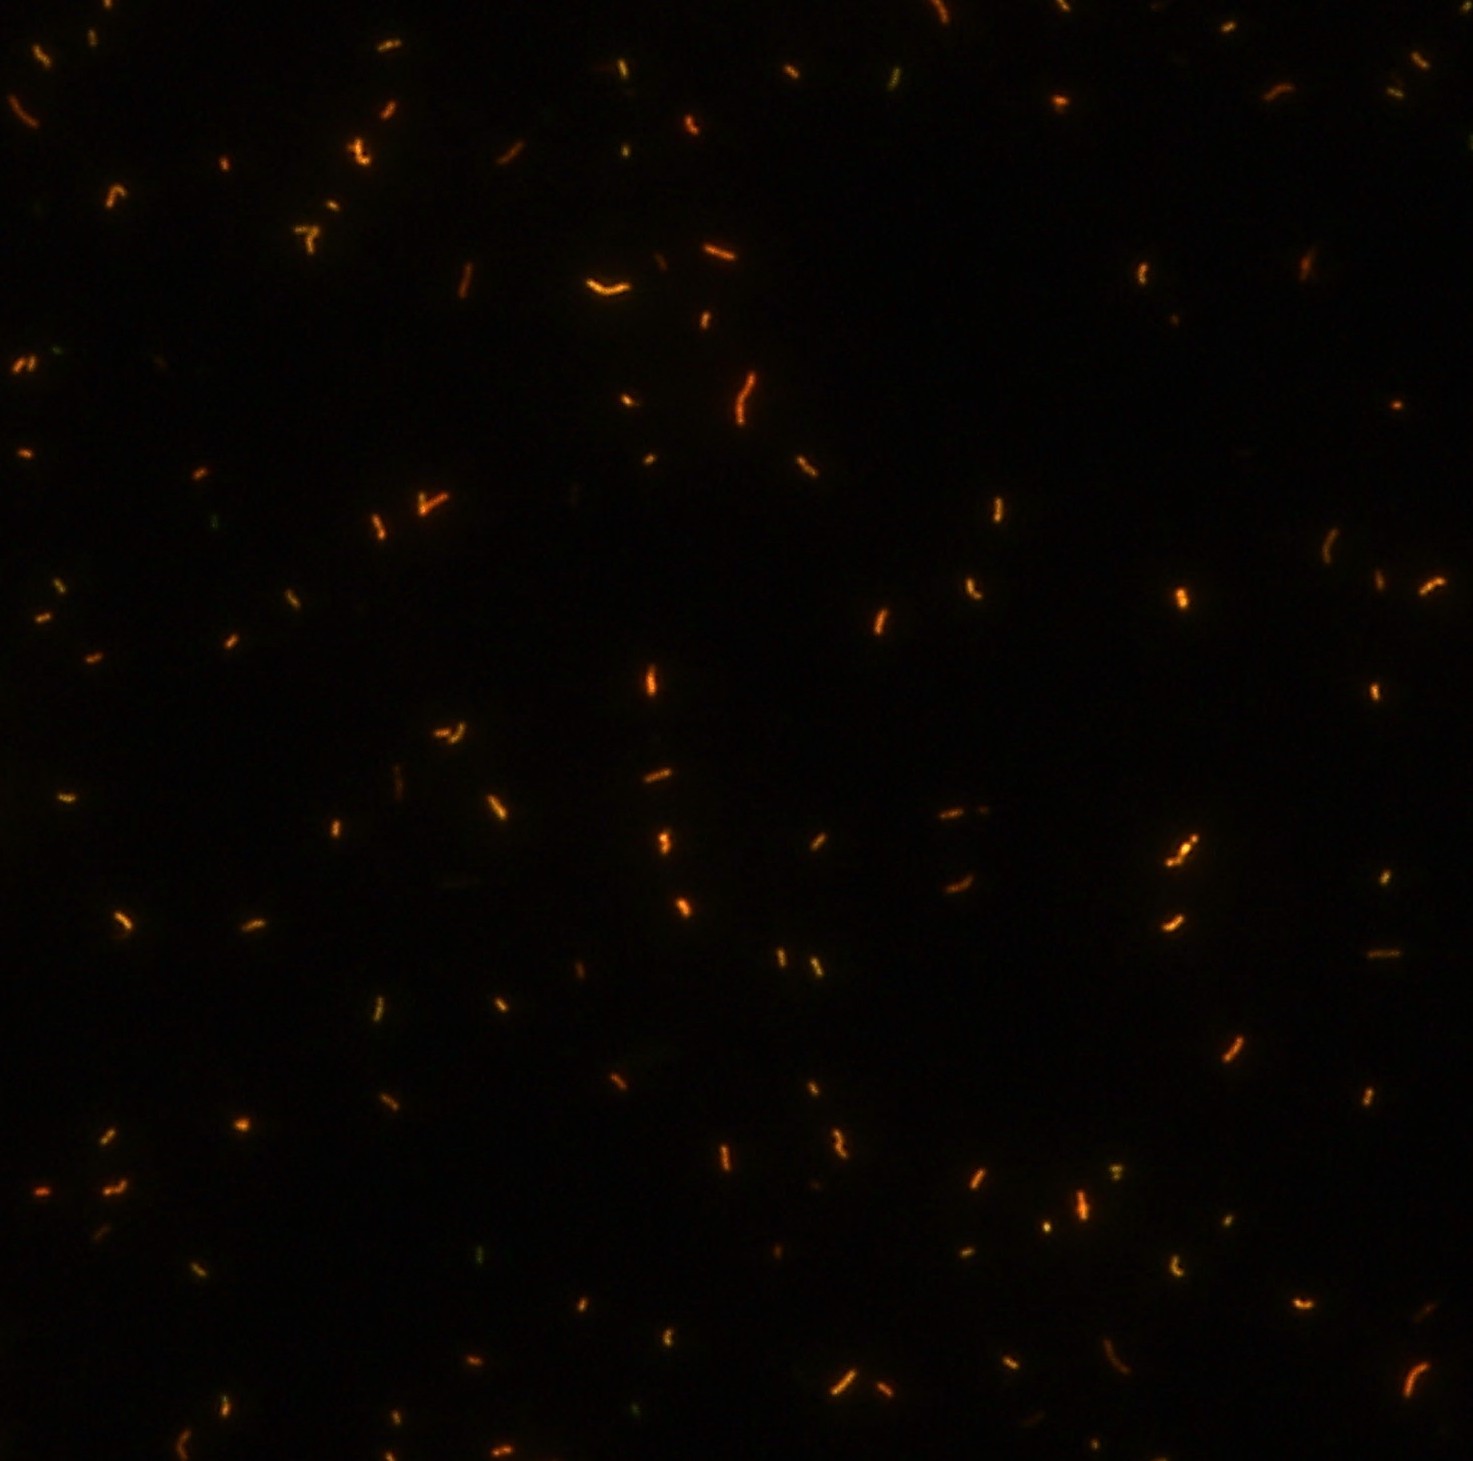

染色結(jié)果 (熒光法×400)

顯微染色技術(shù)是檢測結(jié)核桿菌方法之一。分枝桿菌細(xì)胞壁中含有分枝菌酸,其可以與染料牢固結(jié)合,具有“抗酸性”的特征。熒光染料金胺-羅丹明在染色中與抗酸生物細(xì)胞壁內(nèi)的分枝菌酸相結(jié)合,并耐受酸醇(脫色劑)清洗脫色。反染色劑高錳酸鉀被用來顯出染色生物。AFB(熒光)染色試劑盒設(shè)計(jì)既可用于自動染色機(jī),也可用于手工染色。產(chǎn)品穩(wěn)定性好,染色效果佳。

用于分枝桿菌、諾卡菌等細(xì)菌抗酸染色,包括熒光染色。